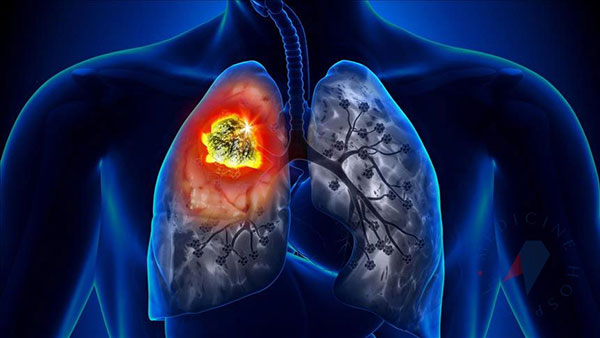

Akciğer kanseri dünyada kanser türleri arasında en sık görülen ve yine en sık ölüme neden olan kanser türü olarak ilk sırada yer alıyor. Öyle ki tüm kanser ölümlerinin yaklaşık 3’te birinden akciğer kanseri sorumlu oluyor. Dünyada her yıl yaklaşık 2,2 milyon kişi sigaranın en önemli risk faktörü olduğu akciğer kanserine yakalanıyor ve 1,6 milyon kişi de bu hastalık nedeniyle hayatını kaybediyor.

Yeni Akit/Ankara Ülkemizde de akciğer kanseri oldukça yaygın görülüyor. 2020 yılında 40 binin üzerinde yeni akciğer tanısı konulduğu belirtiliyor. Akciğer kanseri, genellikle erken dönemlerinde fazla belirti vermemesi veya en tipik belirtisi olan öksürük geliştiğinde sigara içen kişilerin ‘sigara öksürtüyor’ düşüncesiyle hekime geç başvurmaları nedeniyle sıklıkla ileri evrede teşhis ediliyor. Tedavinin gecikmesi de hastanın hayatını kaybetmesine yol açıyor. Acıbadem Ataşehir Hastanesi Göğüs Cerrahisi Uzmanı Prof. Dr. Erdal Okur, oysa gerek cerrahi tedavide gerekse diğer tedavi yöntemlerinde yaşanan önemli gelişmeler sayesinde özellikle erken tanı konabilen ve cerrahi olarak tedavi edilebilen akciğer kanserinden tamamen kurtulmanın mümkün olabileceğini belirterek, “Hastalığın erken döneminde tanı konabilmesi için yüksek riskli olarak belirlenmiş, yoğun sigara içen veya geçmişte içmiş olan 50 yaş üzeri kişilere her yıl düşük radyasyon dozlu bilgisayarlı akciğer tomografi çekimi yapılması öneriliyor. Bu sayede henüz hiçbir belirti vermemiş erken evre akciğer kanserinin yakalanması mümkün olabiliyor” diyor. Peki hangi belirtiler akciğer kanserine işaret ediyor, ne zaman hekime başvurmak gerekiyor? Göğüs Cerrahisi Uzmanı Prof. Dr. Erdal Okur, “1-30 Kasım Dünya Akciğer Kanseri Farkındalık Ayı” kapsamında akciğer kanserinin belirtilerini anlattı; önemli uyarılarda bulundu!

Öksürük Akciğer kanserinin ilk belirtisi genellikle öksürük oluyor. Göğüs Cerrahisi Uzmanı Prof. Dr. Erdal Okur, öksürüğün tümörün havayolunu irrite etmesi veya tıkanıklıklar yapması sonucu geliştiğini belirterek, “Kronik sigara içenlerde özellikle sabahları, bir miktar balgamın eşlik ettiği, kronik öksürük yaşanabiliyor. Ancak önceden de var olan öksürükte artma veya öksürüğün karakterinde bir değişiklik hissedildiğinde hekime başvurmak yaşamsal önem taşıyor” diyor.

Kanlı balgam Kanlı balgam akciğer kanserinin en özgül bulgularından biridir. Akciğer kanserinde ağızdan gelen kanama; derinden öksürükle gelen ve genelde balgamla birlikte, balgam içinde bir damla veya çizgi şeklinde oluyor. “Balgamda kan görülmesi hemen hekime başvurma gerekliliğinin işaretidir” uyarısında bulunan Prof. Dr. Erdal Okur, “Bazen burun ve dişetlerinde de kanama olup ağızdan veya balgamla karışık gelebiliyor. Bu nedenle her ağızdan kan gelmesi mutlaka akciğer kanseri demek değildir. Ancak özellikle orta yaş ve üstü sigara içen kişilerin bu konuda şüpheci olmalarında yarar vardır” diyor.

Nefes darlığı Akciğer tümörünün havayolunu tıkaması veya akciğerlerde tümöre bağlı su toplanması nedeniyle nefes darlığı gelişebiliyor. Kronik sigara içenlerde, kronik obstrüktif akciğer hastalığı (KOAH) sık görülüyor ve bu hastalar nefes darlığı sorunu yaşayabiliyor. KOAH hastalarında akciğer kanseri de geliştiği zaman nefes kapasitelerinde bir miktar daha bozulma yaşanabiliyor. Kişi daha az efor sarf ettiğinde, örneğin merdiven çıkarken veya daha kısa mesafe yürüse bile hemen yorulduğunu hissediyor. Daha önce nefes darlığı yaşamayan kişilerde de fiziksel aktiviteyle nefes darlığı sorunu başlayabiliyor. Tüm bu bulgular hekime danışmayı gerektiren akciğer kanserinin sinyali olabiliyor.

Sık akciğer enfeksiyonu geçirmek Tümör akciğerde havayolunda tıkanıklık yapabiliyor ve bu tıkanıklığın arkasında kalan akciğer kısmında enfeksiyon gelişebiliyor. Antibiyotik ile tedavi edilip düzelse de akciğer enfeksiyonu bir süre sonra tekrarlıyor. Prof. Dr. Erdal Okur, “Dolayısıyla art arda akciğer enfeksiyonu geçiren kişi bu durumda akciğerlerinde havayolunu tıkayan bir sorun olabileceği ihtimalini düşünmeli ve mutlaka hekimine başvurmalıdır.” diyor.

Ses kısıklığı Ses tellerine giden sinirlerden özellikle sol tarafta olanı akciğerin yakınından geçiyor ve bu sinire akciğer tümörünün kendisi veya onun neden olduğu lenf bezi büyümesi bası yaptığı zaman hastanın sesinde tamamen veya kısmi kısılma başlayabiliyor. Ses kısıklığının başka nedenleri olsa da, özellikle akciğer kanseri için risk grubundaki kişilerin bu konuda dikkatli olmaları büyük önem taşıyor.

Göğüs, omuz ve kol ağrısı Göğüs bölgesinde ağrı akciğer tümörünün göğüs duvarına ulaşması durumunda görülüyor. Devamlı künt ve hiç kaybolmayan bir ağrı şeklinde gelişiyor. Göğüs Cerrahisi Uzmanı Prof. Dr. Erdal Okur, “Akciğerlerin en üst tepe kısımlarında gelişen tümörler ise omuz ve kol ağrısına yol açabiliyor. Dolayısıyla başka neden olmadan ve 1-2 hafta içinde düzelme göstermeyen göğüs bölgesindeki ağrı akciğer kanserinin habercisi olabiliyor.” uyarısında bulunuyor.

Kilo kaybı, halsizlik Çoğu kanser gibi akciğer kanserinde de vücutta yıkım artıyor, hastada kansızlık (anemi) gelişiyor. Hasta yavaş yavaş kilo kaybediyor ve kendini halsiz, bitkin hissedebiliyor. Bazen iştahı azalmamış olsa da ve iyi beslense de kilo kaybı devam edebiliyor. Dolayısıyla istemsiz ve diyet yapmadan oluşan kilo kaybı vücutta herhangi bir yerde gelişen kötü huylu tümörden kaynaklanabiliyor.

Nadir görülen diğer belirtileri Boyun bölgesinde beze büyümeleri, yutma zorluğu, kol ve bacaklarda devamlı geçmeyen ağrılar ve hırıltılı solunum gibi diğer belirtiler de aslında ileri evre akciğer kanserinden kaynaklansalar da bazen ilk sinyali olabiliyor.